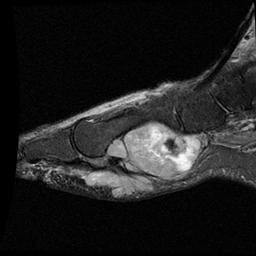

Foot

Heterogenous mass, low signal intensity T1, high signal intensity T2

- may have characteristic triple signal intensity

- area hyperintensity, isointensity and hypointensity